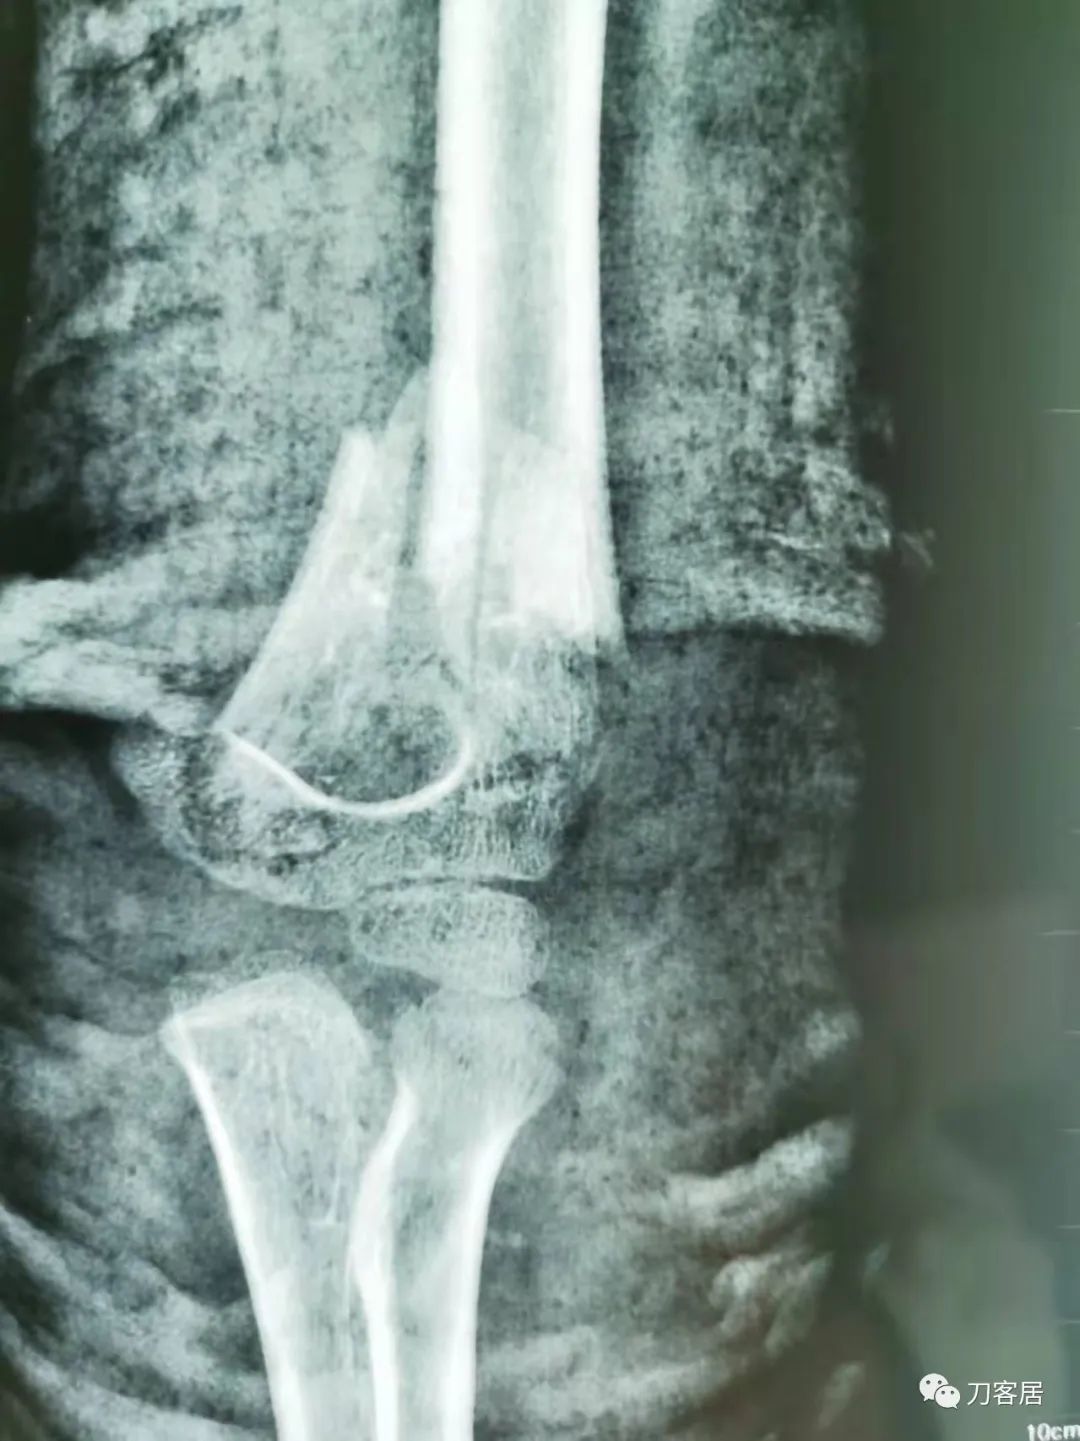

20210922当地省中医院拍摄的石膏外固定正位X线片

20210922当地省中医院拍摄的石膏外固定侧位X线片